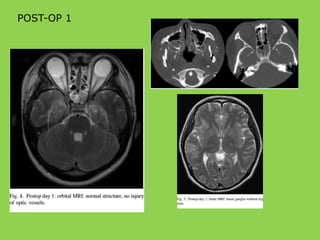

POST-OP 1

POST-OP 19

• Color Doppler– left internal carotid flow

POST-OP 2 MONTHS CONCLUSION •Congenital hypoplasia internal carotid